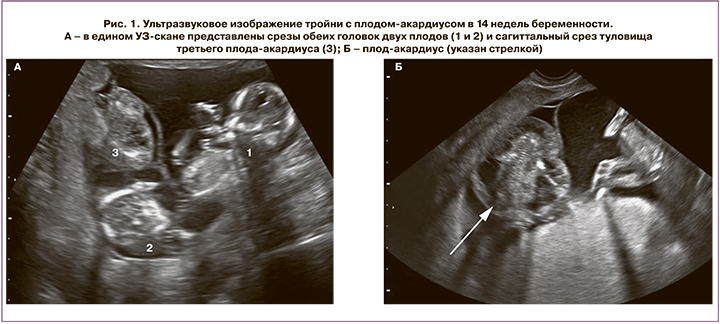

Контрольное УЗИ выполнено в 14 недель, ранее декларированного срока (16 недель) по настоянию семьи. Установлено что два плода соответствуют сроку гестации 14 недель 6 дней (массой 89 г) и 15 недель 1 день (массой 102 г) и не имеют признаков сердечной недостаточности. Максимальная длина акардиуса – 53 мм, масса – 24 г. Поскольку определиться, какой из плодов является так называемой помпой, до момента появления эхографических признаков сердечной недостаточности невозможно, проведен расчет соотношения массы плода-акардиуса к обоим другим плодам, и оно составило 27 и 24% соответственно (рис. 1).

В сроке беременности 16 недель начали подтекать амниотические воды. При УЗИ установлено, что один из плодов массой 120 г соответствует сроку 15 недель 5 дней, ВПР не выявлено, второй плод массой 105 г по фетометрии выглядит на 15 недель 3 дня, третий плод-акардиус длиной 63 мм имеет массу 38 г. У второго плода определяется максимальный вертикальный карман 12 мм, что соответствует выраженному маловодию. При УЗИ через неделю установлено выраженное маловодие уже у двух плодов (рис. 2).